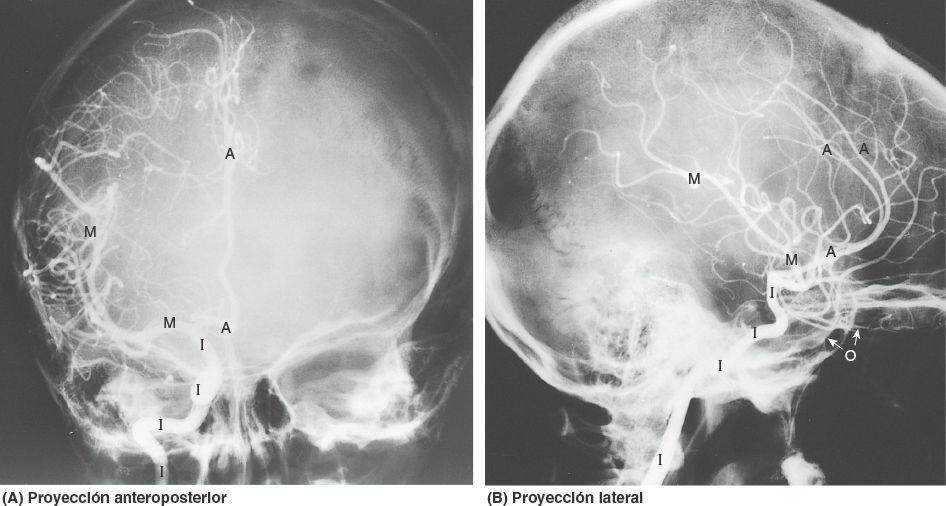

Las arterias carótidas internas se originan en el cuello a partir de las arterias carótidas comunes (fig. 8-39). La porción cervical de cada arteria asciende verticalmente a través del cuello, sin ramificarse hasta la base del cráneo. Penetra en la cavidad cra-neal a través del conducto carotídeo en la porción petrosa del hueso temporal. El curso intracraneal de la arteria carótida interna se ilustra y describe en la figura 8-40 y se expone radio-gráficamente en la figura 8-41. Además de la arteria carótida interna, el conducto carotídeo contiene plexos venosos y plexos carotídeos de nervios simpáticos (fig. 8-40). La arteria carótida interna discurre anteriormente a través del seno cavernoso, con el nervio abducens (NC VI) y en estrecha proximidad con los nervios oculomotor (NC III) y troclear (NC IV), que cursan en el surco carotídeo sobre el lado del cuerpo del esfenoides (figs. 8-31 C y 8-40). Las ramas terminales de la arteria carótida interna son las arterias cerebrales anterior y media (figs. 8-41 y 8-42).

Clínicamente, las arterias carótidas internas y sus ramas se conocen a menudo como circulación anterior del encéfalo. Las arterias cerebrales anteriores se conectan entre sí mediante la arteria comunicante anterior. Cerca de su terminación, las arterias carótidas internas se unen a las arterias cerebrales posteriores mediante las arterias comunicantes posteriores, lo que completa el círculo arterial del cerebro alrededor de la fosa interpeduncular, la depresión profunda situada sobre la cara inferior del mesencéfalo, entre los pedúnculos cerebrales (figs. 8-42 y 8-43).

Además de aportar ramas a las porciones más profundas del encéfalo, las ramas corticales de las arterias cerebrales irrigan una superficie y un polo del cerebro (figs. 8-41 y 8-43 A y B; tabla 8-7). Las ramas corticales de:

- La arteria cerebral anterior irriga la mayor parte de las superficies medial y superior del cerebro y el polo frontal.

- La arteria cerebral media irriga la superficie lateral del cerebro y el polo temporal.

- La arteria cerebral posterior irriga la superficie inferior del cerebro y el polo occipital.